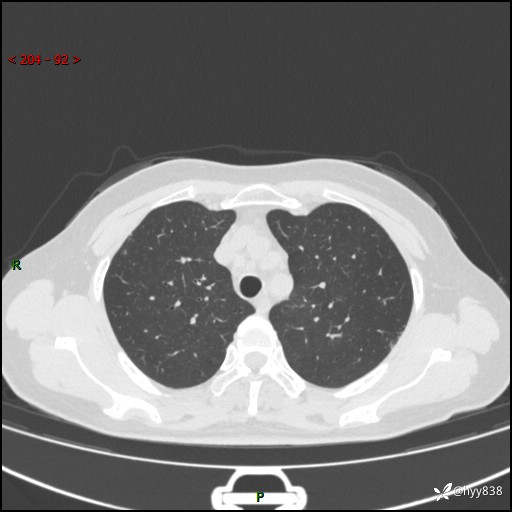

【患者信息】:58岁/女

【主诉】:体检发现肺结节

【检查】:胸部CT平扫+增强